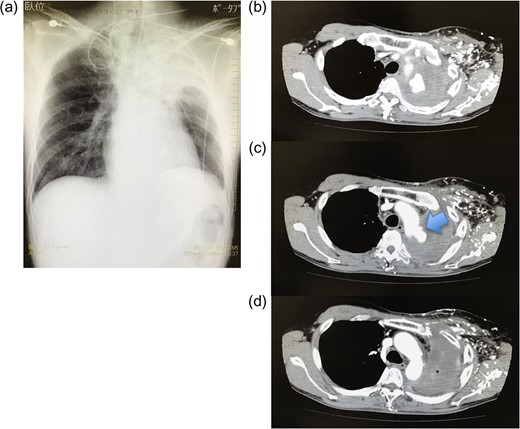

(a) Chest radiography on admission. Consolidation is observed in the left upper lobe. (b–d) Enhanced computed tomography after admission. Extravasation of contrast medium is observed in the distal aortic arch. The entry point is identified distal to the subclavian artery (arrow).